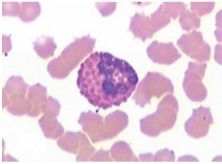

1. monocyten

1. macrofagen

Annotations:

• wanneer monocyten de bloedbaan verlaten.

2. lymfocyten